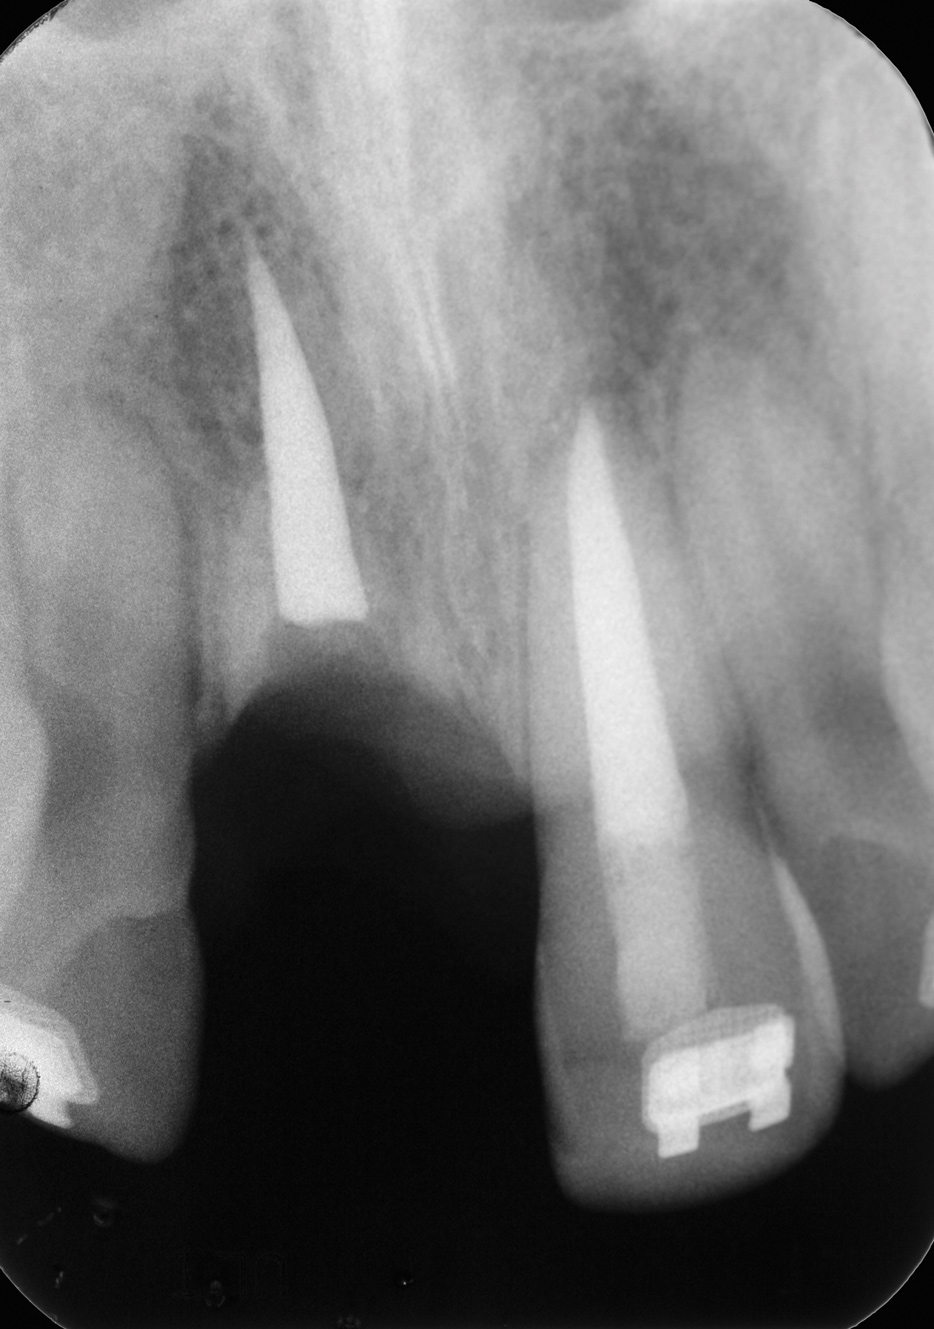

Fig 2. Age 8. Radiograph of teeth Nos. 8 and 9 at initial examination.

Figure 2

The patient's endodontic examination revealed a flexible splint from teeth Nos. 7 through 10 (Figure 1). Tooth No. 8 had a 3 mm x 3 mm class II fracture of the mesioincisal portion of the crown. Tooth No. 9 had a class IV fracture of the crown running labiopalatally from the remaining 2 mm of the crown to bone level on the palatal. A pulpotomy had been performed on the exposed pulp. Both teeth exhibited class III mobility. Teeth Nos. 7 through 10 did not respond to cold testing. None of the teeth were tender to palpation, and only tooth No. 9 had a slight positive response to percussion. Periodontal probings of tooth No. 8 were 4 mm to 5 mm on both the labial and palatal aspects. There was a narrow 12 mm probing on the straight palatal of No. 9; the remaining probing depths were 4 mm to 5 mm.2 A periapical radiograph showed both teeth Nos. 8 and 9 to have incompletely formed roots with wide-open foramina (Figure 2).

Fig 3. Age 10. Radiograph of teeth Nos. 8 and 9, 3 months after the fractured coronal segment of No. 9 was removed. Note the coronal level of the root relative to tooth No. 10.

Figure 3